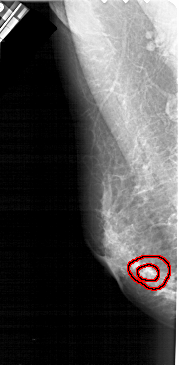

A_1938_1.LEFT_CC

LEFT_CC LINES 4651 PIXELS_PER_LINE 1951 BITS_PER_PIXEL 12 RESOLUTION 43.5 OVERLAY

FILE: A_1938_1.LEFT_CC.OVERLAY

TOTAL_ABNORMALITIES 1

ABNORMALITY 1

LESION_TYPE MASS SHAPE IRREGULAR MARGINS SPICULATED

ASSESSMENT 5

SUBTLETY 2

PATHOLOGY BENIGN

TOTAL_OUTLINES 2

BOUNDARY

CORE